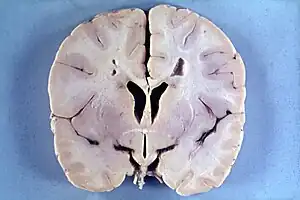

| An MRI of a patient with benign familial macrocephaly (male with head circumference > 60 cm) | |

Macrocephaly is a condition in which circumference of the human head is abnormally large.[1] It may be pathological or harmless, and can be a familial genetic characteristic. People diagnosed with macrocephaly will receive further medical tests to determine whether the syndrome is accompanied by particular disorders. Those with benign or familial macrocephaly are considered to have megalencephaly.